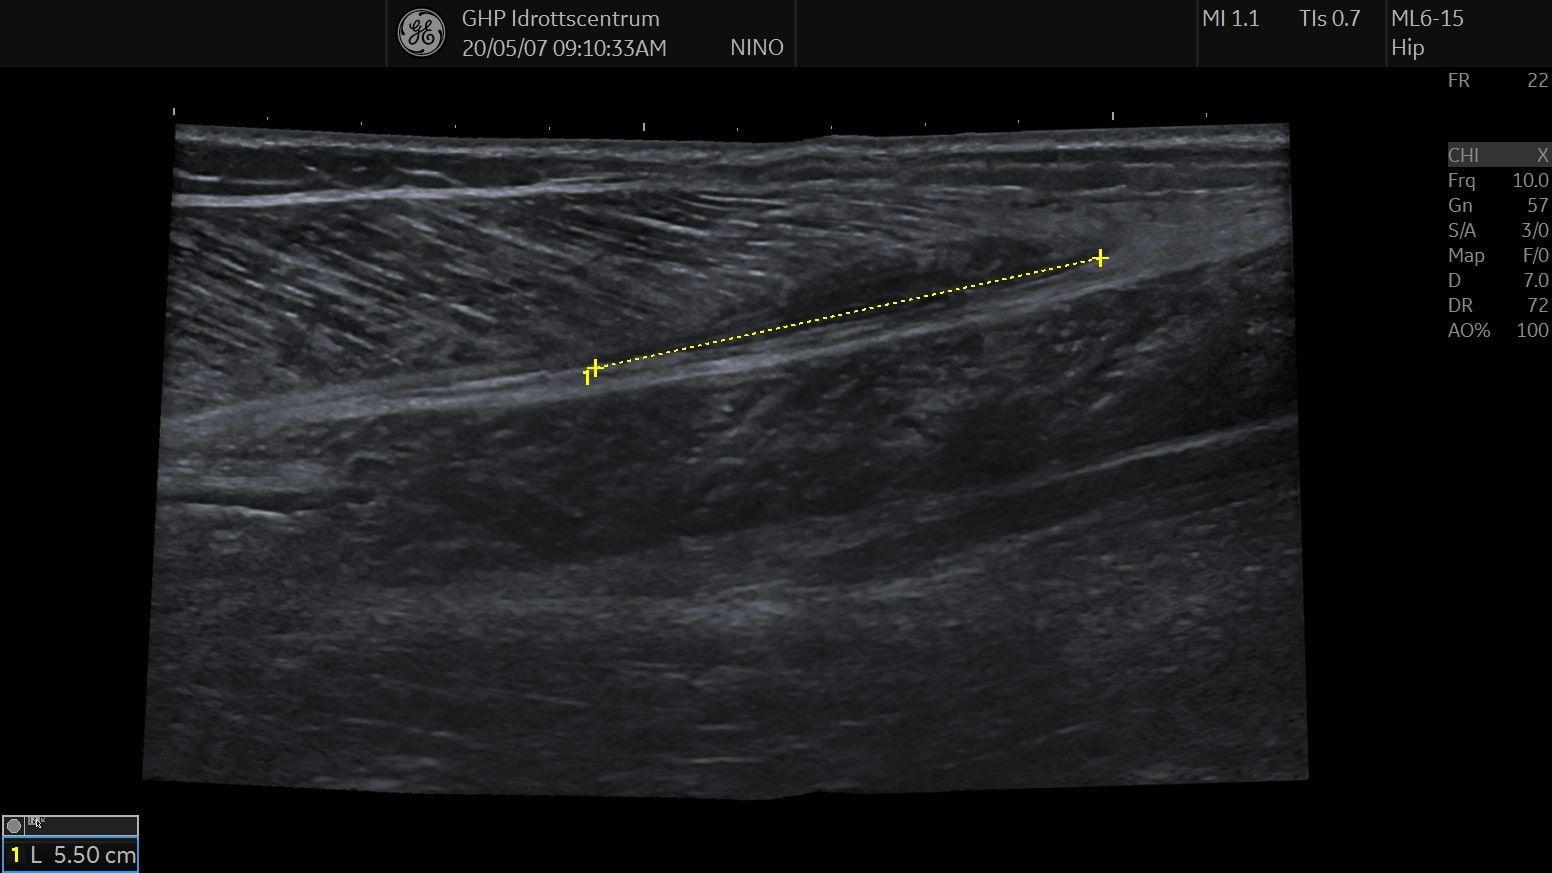

We found a muscle rupture in the medial gastrocnemius, about 2 cm wide and 5 cm long. The patient was given directly information about the diagnosis and sent to Fysio for further conservative treatment.

Gastrocnemius ruptur panoramic